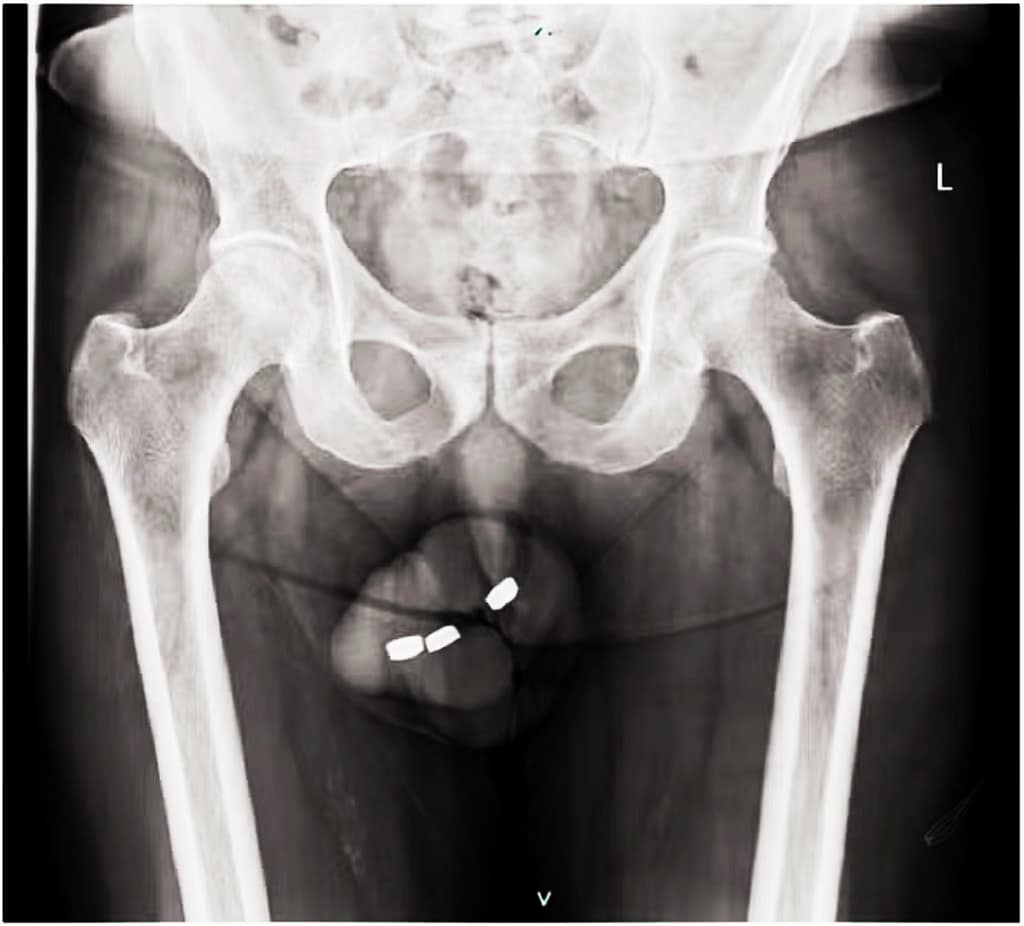

Segundo escrevem os médicos responsáveis pelo paciente, o homem deu entrada na emergência com as três baterias inseridas na uretra. Exames de radiografia revelaram que os objetos eram do tipo botão, com 13,5 mm de largura e 3,2 mm de altura.